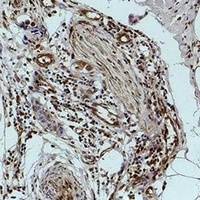

Immunohistochemical analysis of Histone H1 (Phospho-S2) staining in human breast cancer formalin fixed paraffin embedded tissue section. The section was pre-treated using heat mediated antigen retrieval with sodium citrate buffer (Phospho-H 6.0). The section was then incubated with the antibody at room temperature and detected using an HRP conjugated compact polymer system. DAB was used as the chromogen. The section was then counterstained with haematoxylin and mounted with DPX.